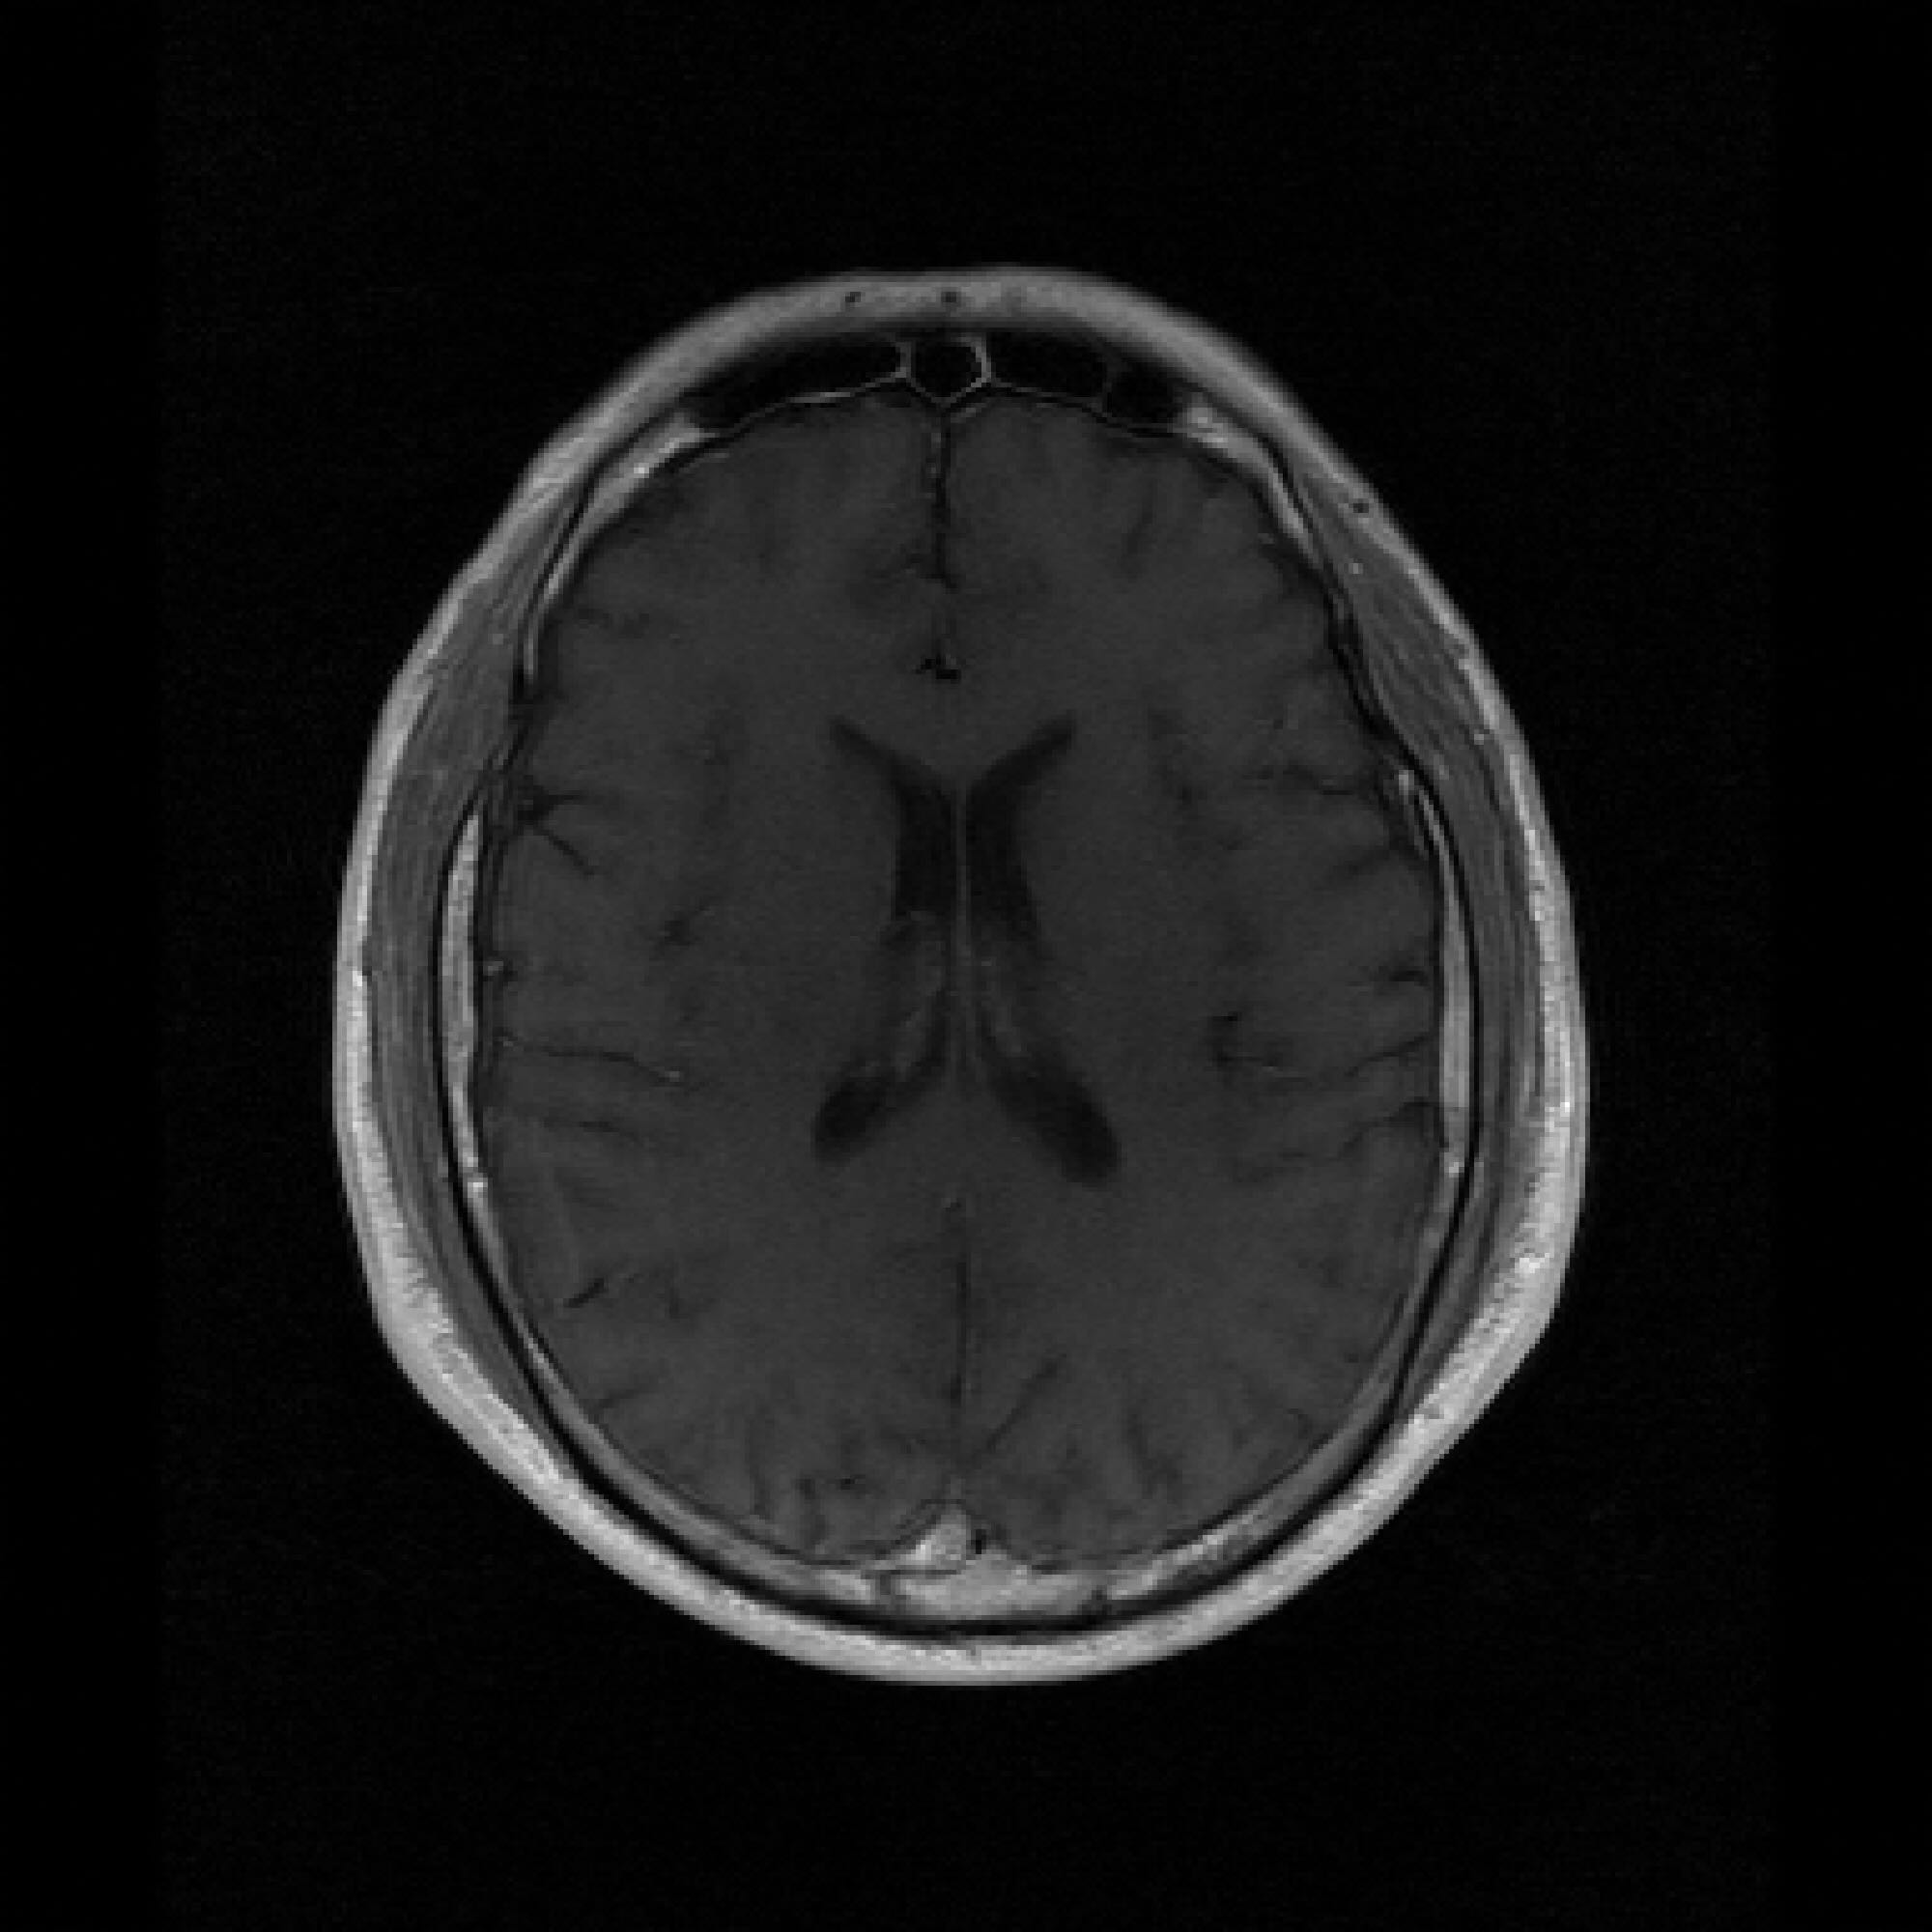

Refer to caption

Figure 3: Pixel-wise standard deviations of reconstructions across 10 random k-space sampling masks (R=7R=7) of the same slice. Top to Bottom: models trained on 100, 500, and 1000 slices. PaDIS-MRI consistently exhibits lower pixel-wise variance (fewer bright regions) than FastMRI-EDM across training sizes and contrast types, indicating more stable reconstruction.

Figure 3 visualizes these standard deviation maps, with brighter regions indicating higher variability between reconstructions. Across the 100-slice, 500-slice, and 1000-slice training regimes, PaDIS-MRI exhibits noticeably lower uncertainty compared to FastMRI-EDM, with the largest differences occurring at the smaller training dataset sizes. This suggests that decomposing the reconstruction problem into localized patches enables more stable learning of anatomical features, resulting in more reliable and consistent predictions from limited training data.